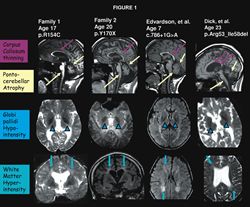

ResearchersThe resulting disease has been named Fatty Acid Associated Neurodegeneration (FAHN). Patients with FAHN experience significant dystonia, like other forms of NBIA, but also exhibit significant ataxia and weakness. Visual problems can result from optic nerve atrophy and nystagmus. In NBIA, MRI scans often provide physicians with the first clues as to the cause of a patient’s symptoms. In FAHN patients, MRI scans show iron deposits in the globus pallidus, similar to other forms of NBIA. FAHN patients also show a decrease in the size of the cerebellum, another region important for movement. Finally, FAHN patients demonstrate abnormal white matter on MRI. In the past, this may have led physicians away from considering a diagnosis of NBIA, although it is now known that these findings can occur in some forms of the disease.

Paper Figure “The characterization of FA2H has led to new concepts in the understanding of NBIA biology,” said Dr. Kruer. "These findings suggest previously unrecognized connections between forms of NBIA. Further characterizing the roles of these pathways in the genesis of disease will be an important step in ultimately developing therapeutics for this devastating neurodegenerative disorder.”